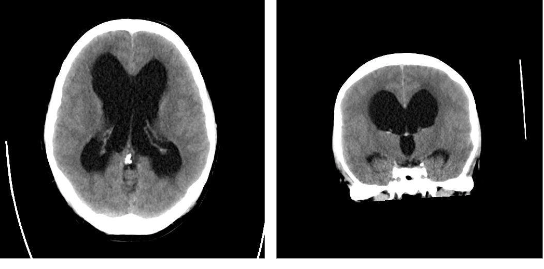

Which bone is fractured? [1]

Acceptable responses: *temporal bone, right temporal bone, temporal, right temporal*